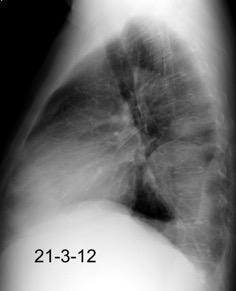

Tromboembolismo pulmonar Diafragma elevado 20%

Atelectasia crónica de LLI en paciente con enfermedad neuromuscular.